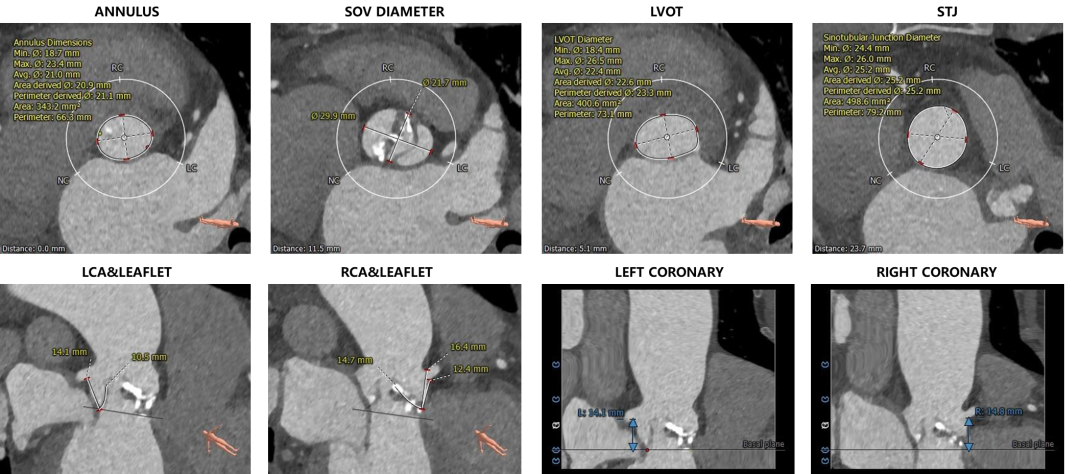

外周血管及主动脉弓解剖:

外周血管概览